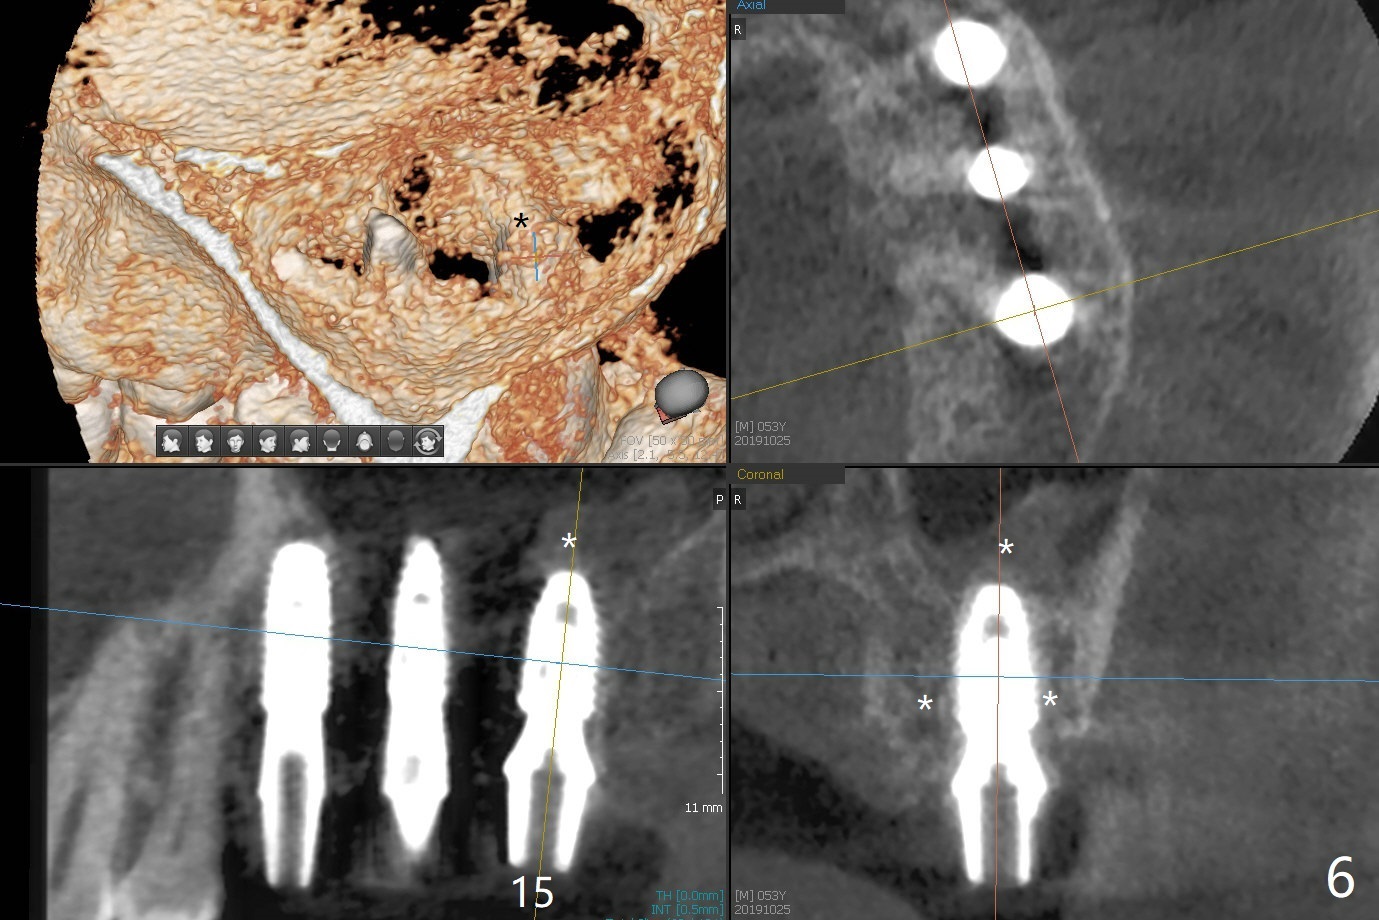

Extraction of abutment teeth associated with the loose FPD is not as easy as expected. Bony anchor placed at #14 (Fig.1 B) becomes loose while initial osteotomy a 2.2 mm drill at #13 for trajectory confirmation. The sinus membrane perforates at #15 when the sinus probe is being used. Luckily the perforation appears to be repaired with 2 pieces of PRF; sinus lift is assisted with a 4.5x10 mm dummy implant (Fig.2 *). Sinus lift at #14 is difficult and incomplete because of small osteotomy (Fig.3,5). In fact there is no sinus infection postop. Splinted immediate provisional is fabricated, but should be sectioned for individual units to form gingival scallops with distinct papillae. Three months postop, the splinted provisional is removed. The abutment at #14 is supragingival and is changed to 4.5x7(3) mm one. Individual temporary crowns are fabricated. Two weeks later, a small papilla forms between #14 and 15, while the temp at #13 is lost. The abutment at #13 changes to 4.5x7(5) mm one (Fig.7) with a new provisional, whereas those at #14 and 15 relined. In fact the abutment at #15 is incompletely seated (<) probably related to contact with the mesial crest (*). An abutment with smaller diameter and longer cuff at #15 seems to be completely seated (Fig.8,9, as compared to Fig.7). Following screw torque at 30 Ncm, impression is taken.